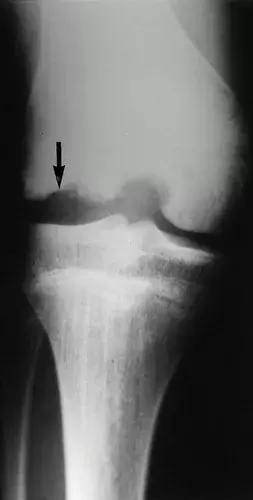

图9:68岁男性,患有长期神经梅毒,膝关节的神经性骨关节病。X线片显示 股骨远端变形,形状像鸡腿。 胫骨横向半脱位,伴有外翻角。 存在明显的关节周围骨质碎屑。 在梅毒患者中,骨关节病最常影响膝关节。